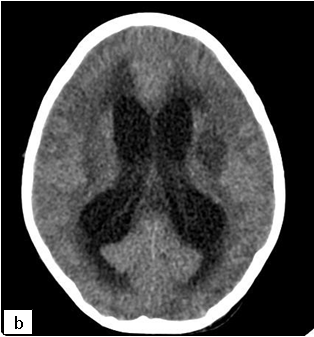

On cranial CT, PML lesions may appear as hypodense patchy or confluent white matter regions. Typical MRI features include single or multiple non-enhancing, non-space-occupying, predominantly white matter lesions commonly involving the frontal and parieto-occipital subcortical white matter.